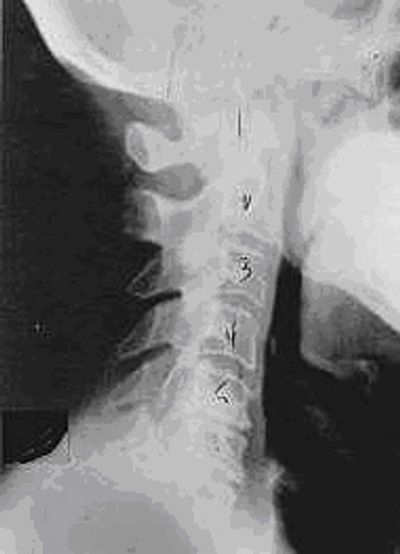

Phase One Subluxation Degeneration

Phase One Subluxation Degeneration is seen in subluxations that have been present for up to twenty years. This phase is characterized with a loss or change in the normal curve in the spine. In many instances a patient will have a straight neck. This is often called military neck posture. In some cases, the curve starts to reverse and go the wrong way as in this example. The disc spaces have also begun to exhibit a slight change in shape. They begin to shrink or get smaller. On a positive note, the bodies of each of the vertebrae (the white square part) still exhibits clean clear borders. Segmental motion, meaning movement between two adjacent vertebrae may be abnormal. However overall motion is usually not affected in this phase of subluxation degeneration. Chiropractic reconstructive care for phase one subluxation degeneration can take from 6 to 18 months. More than 80% of people with Phase One Subluxation Degeneration have no pain. Therefore, if left uncorrected, phase one continues to progress with time until it eventually reaches the next phase.